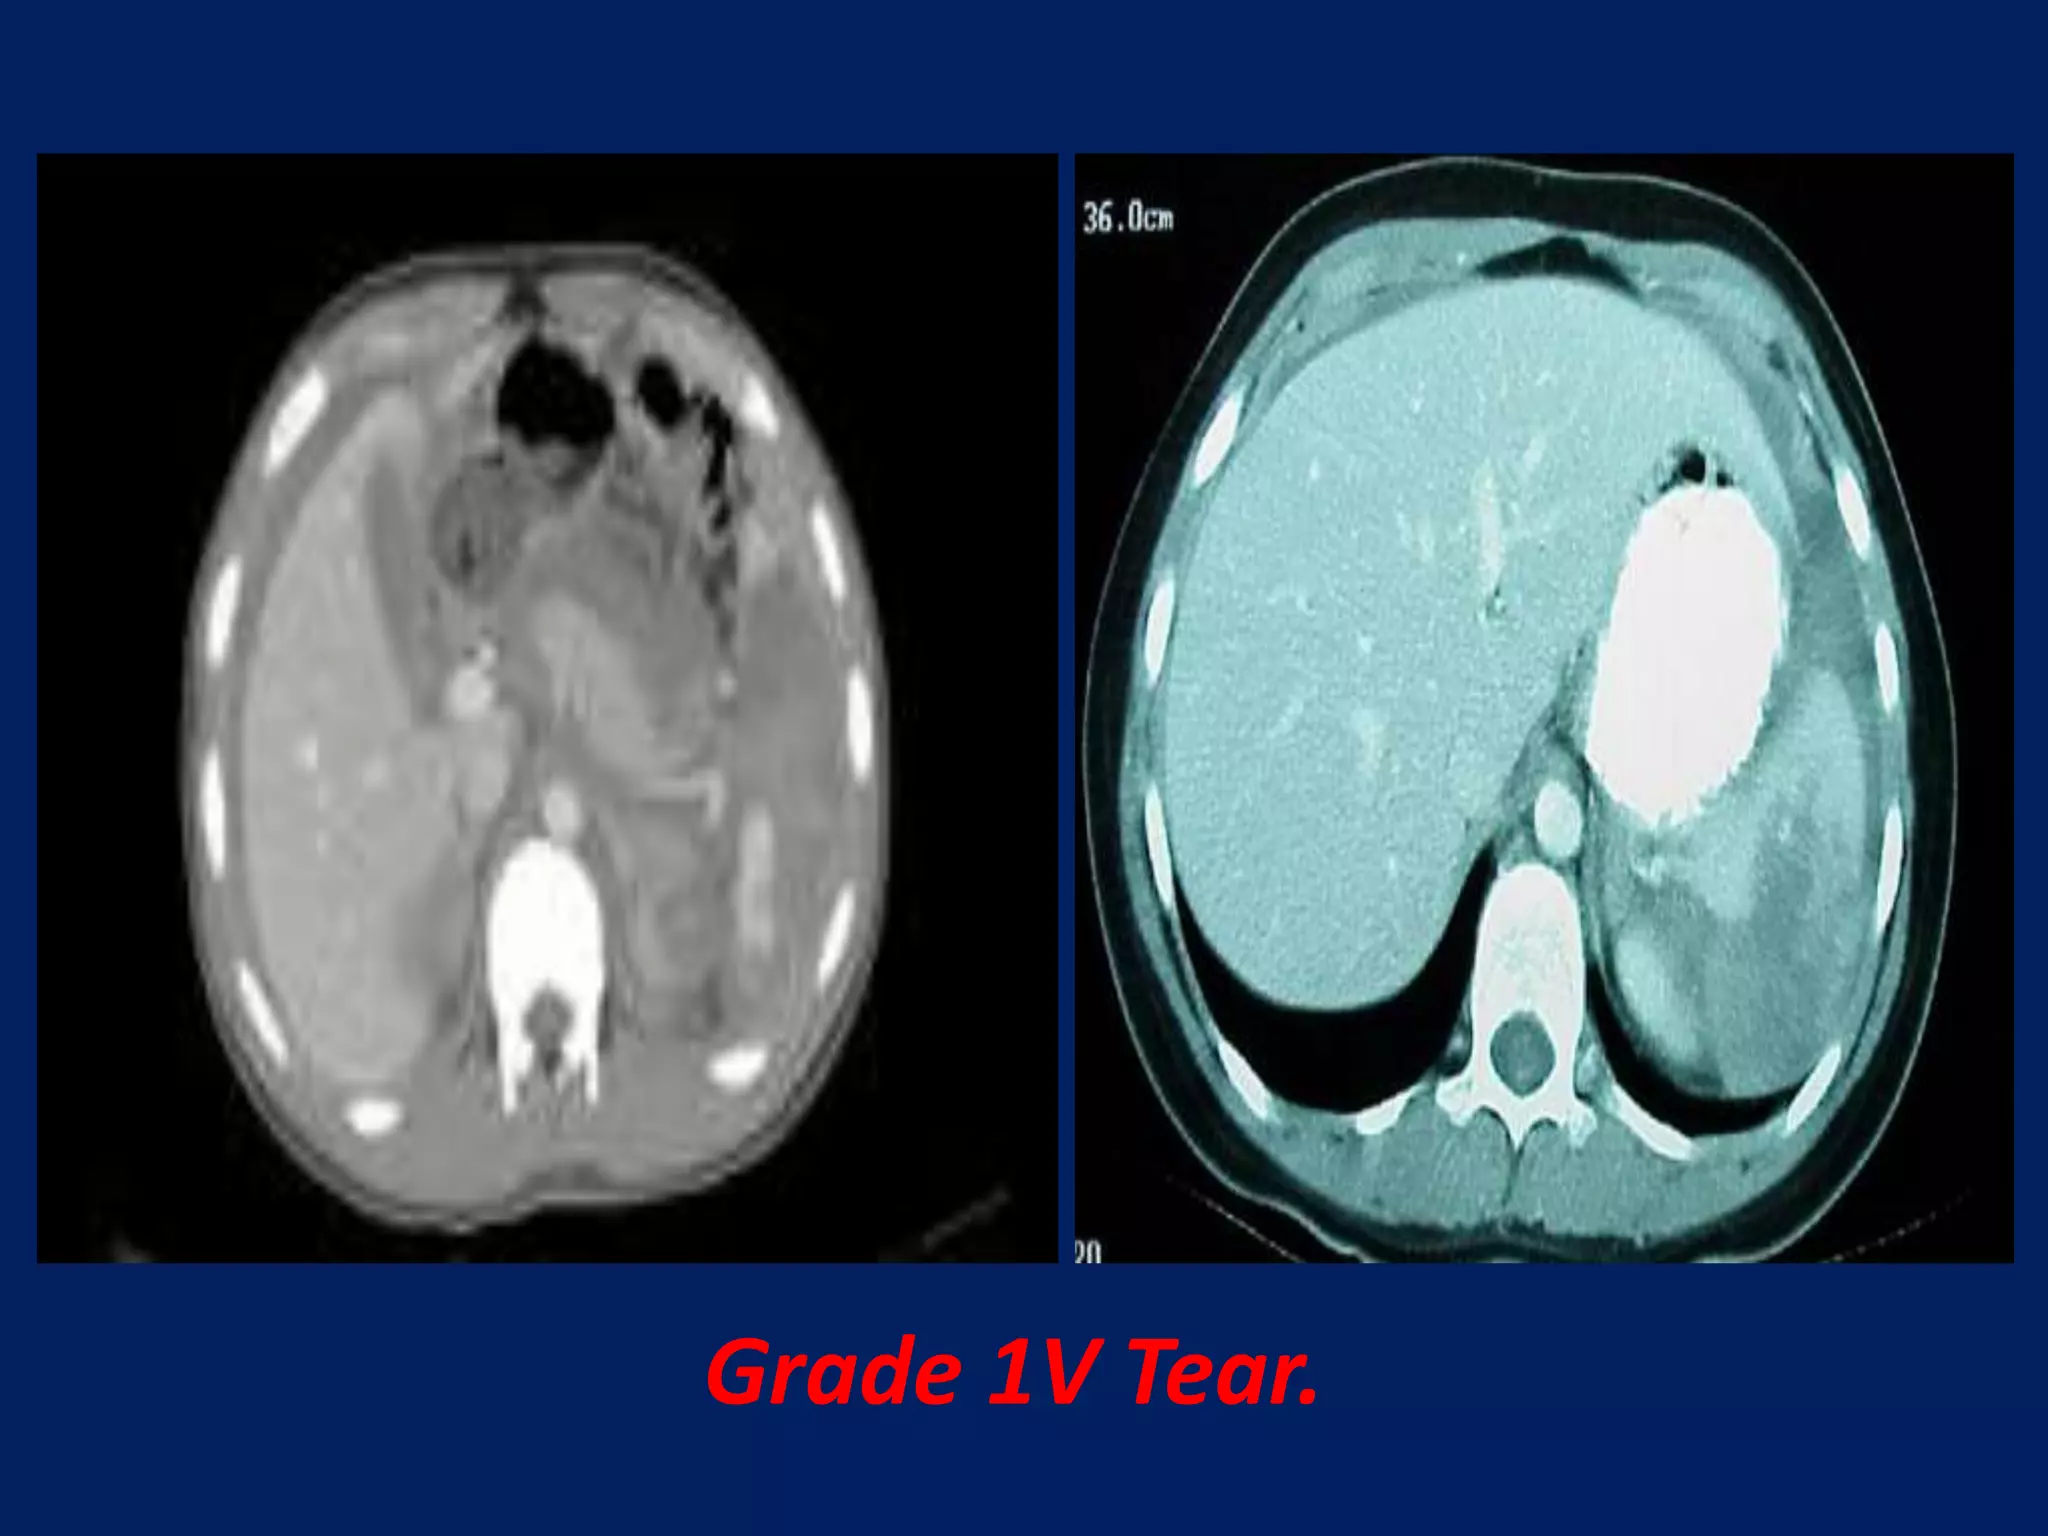

This document discusses imaging of the spleen and summarizes various congenital anomalies and pathologies that can affect the spleen. Some common congenital anomalies mentioned include accessory spleens, asplenia, polysplenia, and splenic fusions. Acquired conditions like repeated infarctions, infiltration, tumors, and cysts can also cause splenomegaly or functional asplenia. Wandering spleen is discussed as a rare congenital anomaly where the spleen lacks attachments and is mobile within the abdomen. Various grades of splenic lacerations and examples of splenic imaging findings are also briefly summarized.